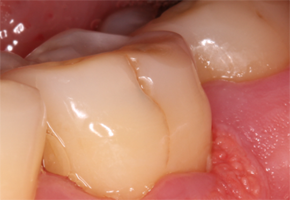

구내염의 가지 수에는 첫 번째로 궤양의 종류인 아프타성 궤양이 있어요. 뺨과 혀, 입술 안쪽에서 생기는 붉은 고리 속 옅은 노란색 궤양의 형태를 보입니다.